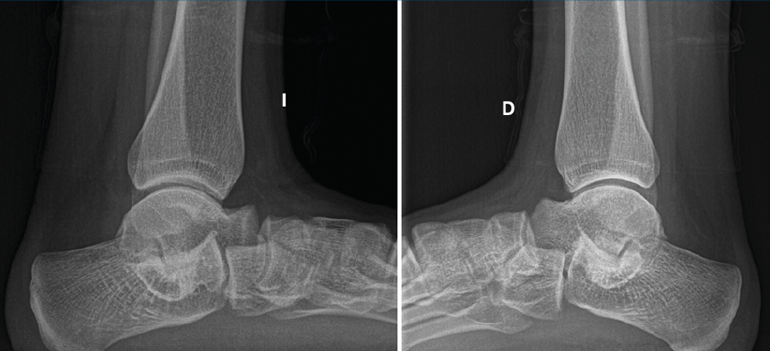

Se trata de una de las causas más comunes del pie plano rígido doloroso en la población pediátrica(9,10,11). El dolor es el síntoma predominante(12,13,14) y de consulta, especialmente tras la actividad física. Los esguinces de repetición, desaxaciones, pies planos y contracturas de peroneos son también formas de presentación habituales (Figura 2). Llegaremos al diagnóstico de dicha patología por sospecha clínica y radiológica, y confirmación por tomografía axial computarizada (TAC) y eventualmente resonancia magnética nuclear (RMN)(15)(Figura 3).

Se trata de una paciente mujer de 27 años de edad, auxiliar sanitaria, con antecedentes de asma, depresión y psoriasis, que presenta un pie izquierdo plano valgo doloroso de 24° de valgo talar, por sinostosis calcaneoastragalina posterior. Dicha paciente presentaba una clínica de dolor en el seno del tarso y los tendones peroneos laterales. Como pruebas complementarias, se realizaron radiografías en carga de los pies y los tobillos, TAC y RMN del tobillo afecto. Se diagnostica de coalición tarsal de tipo 3 de la clasificación de Rozansky(26). Las articulaciones tibioperoneoastragalina y subtalar están preservadas clínica y radiológicamente. El balance articular es de: flexión = 45°; extensión = 15°; inversión = 5°; eversión = 0°. La escala de la American Orthopaedic Foot and Ankle Society (AOFAS) para el tobillo izquierdo presentaba un valor de 60 (20-35-5). Los ángulos radiológicos iniciales son: Moreau-Costa-Bartani interno = 143°; declinación talar = 25,8°; Meary = 9,9°; Kite = 25,5°; taloescafoideo = 54,6° (Tabla 1).

Se trata de una paciente mujer de 18 años de edad, higienista dental, sin antecedentes patológicos de interés, que presenta pies planos valgos bilaterales dolorosos, el derecho de 23° y el izquierdo de 21° de valgo, por sinostosis calcaneoastragalina media en ambos pies. En ella observamos básicamente una clínica de dolor en el seno del tarso, con déficit de movilidad de la articulación subtalar en ambos pies. Se realiza estudio mediante radiografías de los pies y los tobillos en carga y TAC de ambos pies (afectación bilateral). Radiológicamente, las articulaciones tibioperoneoastragalina y subtalar están preservadas. Se diagnostica de coalición tarsal de tipo 4 de la clasificación de Rozansky(26). El balance articular es de: flexión = 45°; extensión = 20°; inversión = 0°; eversión = 0°. La escala de la AOFAS para el tobillo derecho presentaba una puntuación de 62 (20-37-5). Los ángulos radiológicos iniciales son: Moreau-Costa-Bartani interno = 141°; declinación talar = 18,4°; Meary = 6,3°; Kite = 25,6°; taloescafoideo = 48,3°.